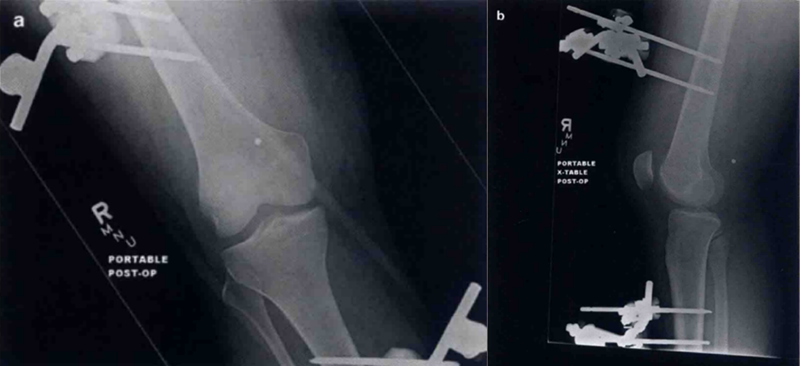

尽管该分型系统已被使用许多年,但是仍有一定的局限性。胫骨和股骨位置分型对于同时并存的损伤诊断十分有用,如血管或神经损伤。前向和后向脱位很有可能合并围动脉损伤。然而,由于所有的分型都有可能合并血管损伤,不管是哪种脱位,医帅都应高度警惕是否存在血管损伤。位置分型也可以协助确定复位方式,但是大多数脱位通过轴向牵引很容易复位。当医师在确定后外侧脱位时该分型十分有用(图3)。警惕股骨内侧髁钮扣孔样通过内侧关节囊组织,卡压陷入的内侧副韧带或内侧结构时,通常是不能够复位的。后外侧膝关节脱位特征性的标志是沿着内侧膝关节间隙的内侧皮肤的“深沟征”(medial skin furrowing),通常会显示出股骨髁远端的关节面的轮廓。对这种情况有必要迅速复位,否则股骨内侧髁的压迫会使皮肤和(或)内侧副制带坏死。发生后外侧脱位时骨科医师应高度警惕切开复位的可能性。同时。这种脱位也经常合并腓总神经损伤。

图3 a为后外侧脱位的印象学检查。这种膝关节脱位是可复性的,需要做一个将MCL插入关节的开放性复位。b和c分别是复位后的前后位片和侧位片